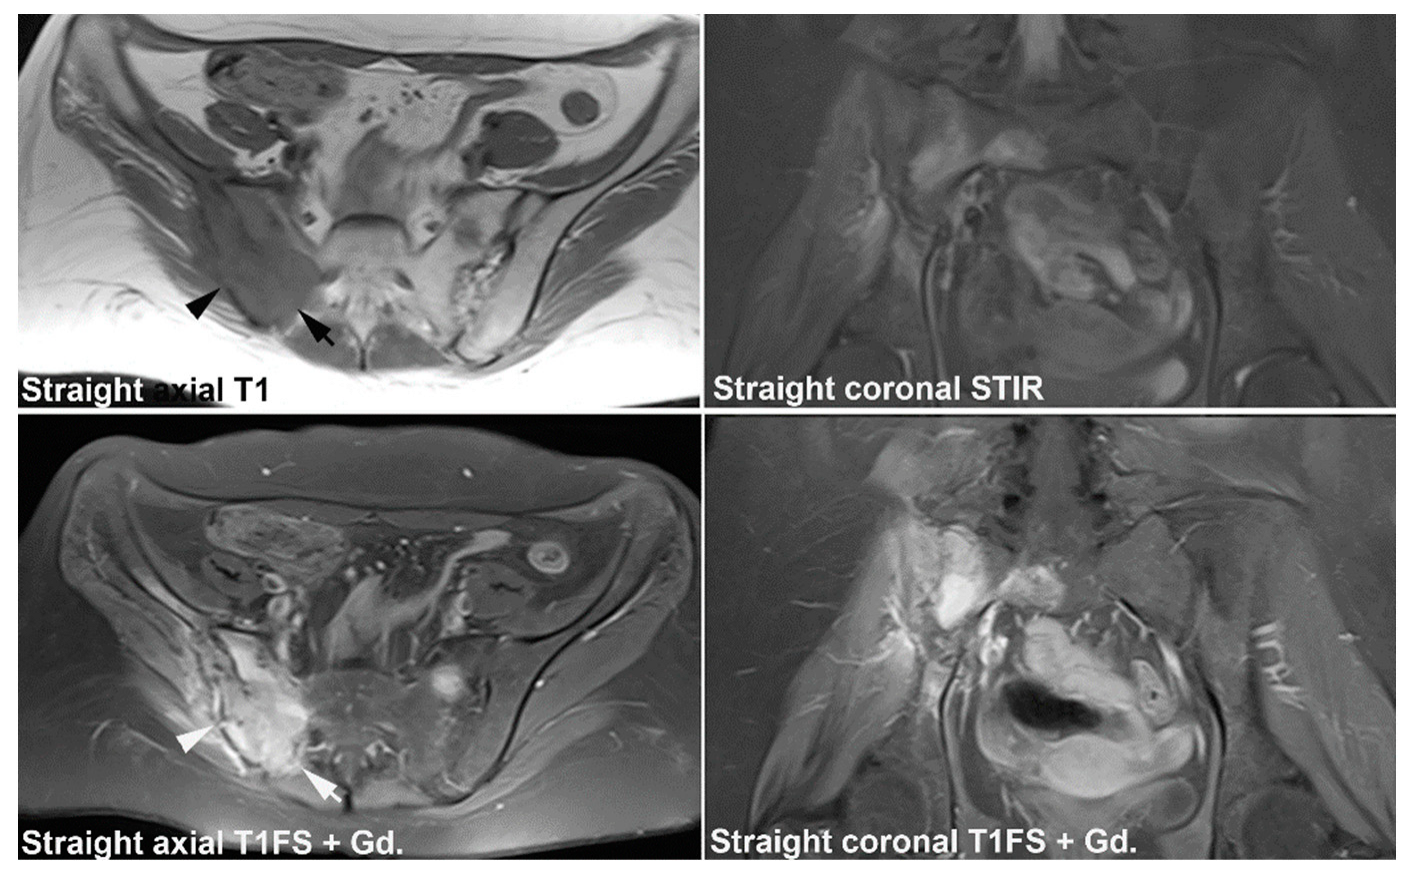

9. Infectious Sacroiliitis